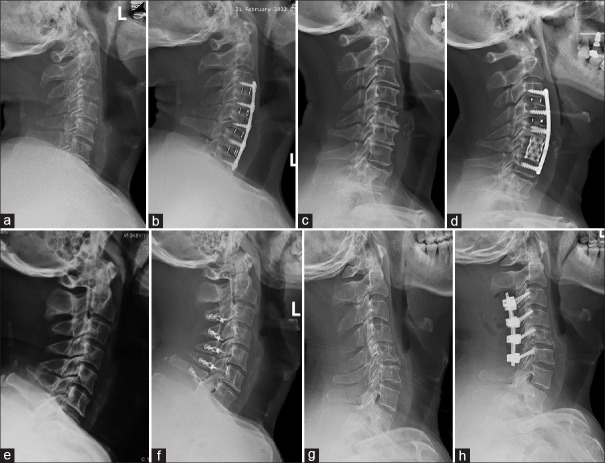

Materials and methods: Three hundred sixty-six patients diagnosed with CDD were enrolled from 2018 to 2023. Grouped based on T1S-CL, a value of T1S-CL <20° defined as a matching group, and a value of T1S-CL >20° comprised a matching group. All patients underwent only cervical anterior or posterior approach surgery. Clinical indexes of the Japanese Orthopedic Association (JOA) score, Visual Analog Scale (VAS) and neck disability index (NDI), and radiologic parameters of T1S, CL, and sagittal vertical axis (C2-7 SVA) were recorded and analyzed.

Results: Before surgery, there were significant differences in factors between the two groups for CL, T1S, and T1S-CL (P < 0.05). Postoperatively, clinical indexes and radiological parameters changed significantly (P < 0.001) in each group. There are significant correlations indicated between T1S and CL (P < 0.05) except for one in a mismatching group of posterior approach (P > 0.05) postoperatively. There are significant correlations indicated between T1S-CL and T1S, CL (P < 0.05) in two groups of anterior approaches except for posterior approaches (P > 0.05).

Conclusion: T1S-CL-based surgical approaches indicate that cervical anterior approaches are superior to posterior paths in improving and optimizing sagittal alignment. Posterior approaches may impair alignment in situations of T1S-CL <20°, and deteriorate malalignment established with conditions of T1S-CL >20°.